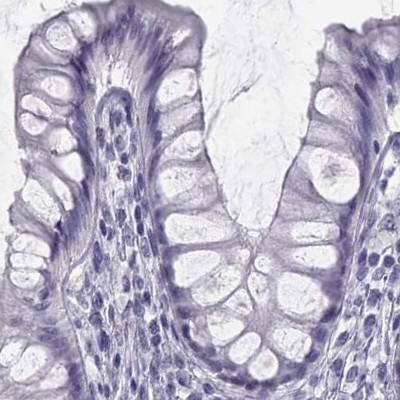

Immunohistochemistry analysis in human seminal vesicle and lymph node tissues using Anti-SEMG1 antibody. Corresponding SEMG1 RNA-seq data are presented for the same tissues.